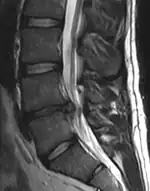

The majority of spinal disc herniations occur in the lumbar spine (95% at L4–L5 or L5–S1).[21] The second most common site is the cervical region (C5–C6, C6–C7). The thoracic region accounts for only 1–2% of cases. Herniations usually occur postero-laterally, at the points where the annulus fibrosus is relatively thin and is not reinforced by the posterior or anterior longitudinal ligament.[21] In the cervical spine, a symptomatic postero-lateral herniation between two vertebrae will impinge on the nerve which exits the spinal canal between those two vertebrae on that side.[21] So, for example, a right postero-lateral herniation of the disc between vertebrae C5 and C6 will impinge on the right C6 spinal nerve. The rest of the spinal cord, however, is oriented differently, so a symptomatic postero-lateral herniation between two vertebrae will impinge on the nerve exiting at the next intervertebral level down.[21]

Herniated lumbar disc

Lumbar disc herniations occur in the back, most often between the fourth and fifth lumbar vertebral bodies or between the fifth and the sacrum. Here, symptoms can be felt in the lower back, buttocks, thigh, anal/genital region (via the perineal nerve), and may radiate into the foot and/or toe. The sciatic nerve is the most commonly affected nerve, causing symptoms of sciatica. The femoral nerve can also be affected and cause the patient to experience a numb, tingling feeling throughout one or both legs and even feet or a burning feeling in the hips and legs.[22] A herniation in the lumbar region often compresses the nerve root exiting at the level below the disc. Thus, a herniation of the L4–5 disc compresses the L5 nerve root, only if the herniation is posterolateral.